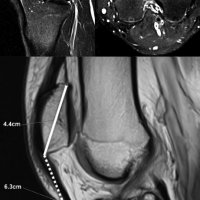

ACHILLES TENDON XANTHOMAS

Achilles tendon xanthomas are painless soft tissue masses occurring most commonly at the distal one-third of the tendon and are usually bilateral and symmetrical.

In plain radiograph, this condition appearas as soft tissue densities in the Achilles tendon.

Ultrasound reveals increased AP thickness of the tendon >7 mm in males and >6 mm in females, also loss of normal tendon appearance with multiple hypoechoic foci within the tendon.

MRI shows focal thickening of the tendon with increased AP diameter, loss of the normal anterior concavity of the tendon with speckled appearance of the tendon, hyperintense on T1- and T2-weighted images.